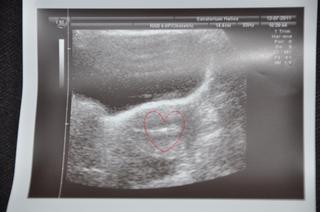

@bublenudle cerstvej zazitek - na monitoru pred sebou ti ukazou embryjko, doktor mi ho popsal a slecna v laboratori ho nasala do te transfer hadicky a donesla k transferu, pak na ultrazvuku ukazovali zavadeni , je to takova mala fazolka a jeste mi vytiskly fotecku, takze vsechno zdokumentovano 🙂

@cuddle moc děkujeme za nádhernou zprávičku o postupu a hlavně za úžasný obrázek se kterým jsi se s námi podělila. Vypadá to tam útulně... takže nevidím důvod proč by se tam prckovi nemělo líbit. 😉 Jen ať se mu tam pěkně daří a vyřiď mu (jí) že tety chystají podobné domečky pro kamarády a že musí pěkně růst, aby ho pak naši prcci nepřeprali 😉